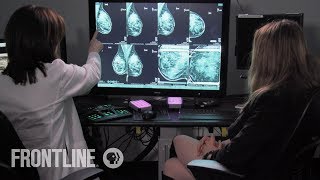

Using Artificial Intelligence To Detect Breast Cancer An AI Scientist Turned a Breast Cancer Diagnosis Into a Tool to Save Lives | FRONTLINE

Using Artificial Intelligence To Detect Breast Cancer An AI Scientist Turned a Breast Cancer Diagnosis Into a Tool to Save Lives | FRONTLINE